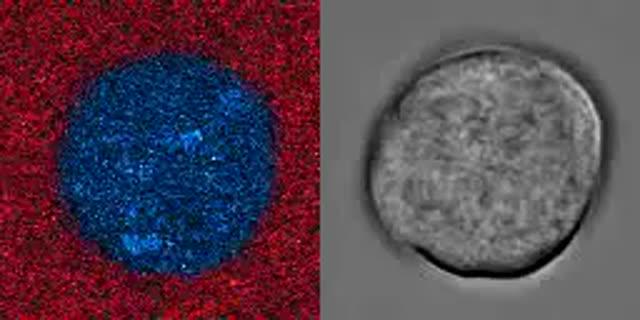

video: A megakaryocyte displaying calcium waves (blue) and binding of fibrinogen (red) after being stimulated. This material relates to a paper that appeared in the Jan. 22, 2020, issue of Science Translational Medicine, published by AAAS. The paper, by A.P. Bye at University of Reading in Reading, UK; and colleagues was titled, " Ca2+ waves coordinate purinergic receptor-evoked integrin activation and polarization." view more

Credit: [Credit: A.P. Bye <i>et al., Science Signaling</i> (2019)]